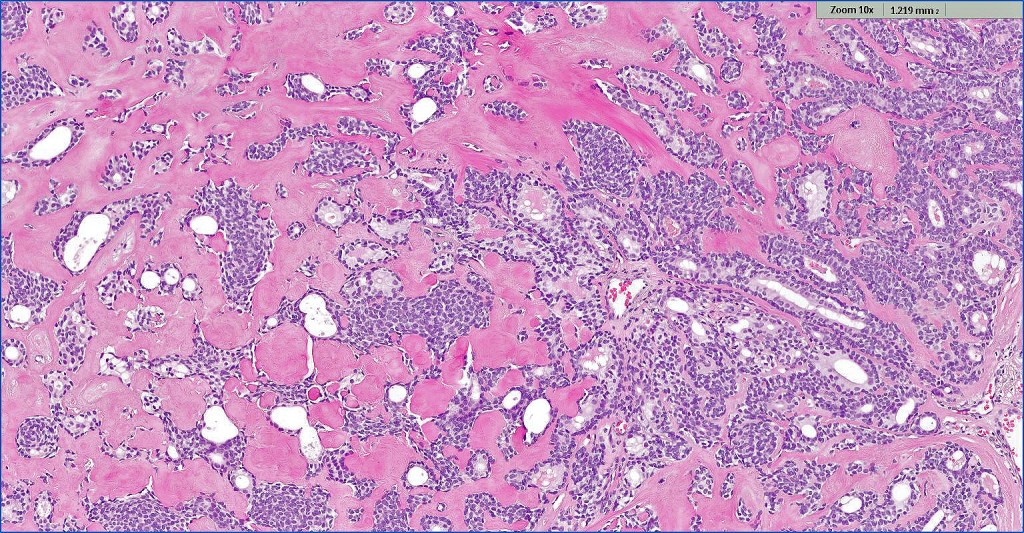

Histological features

•Solid or cystic sharply defined nodule in dermis sometimes extending into subcutaneous fat

•Generally composed of an admixture of small eosinophilic cells & glycogen-rich larger clear cells

•Round to oval vesicular nuclei with small nucleoli or hyperchromatic nuclei

•No pleomorphism & scanty or no mitoses

•Ductal and glandular differentiation

•Squamous differentiation

•Hyaline collagenous stroma